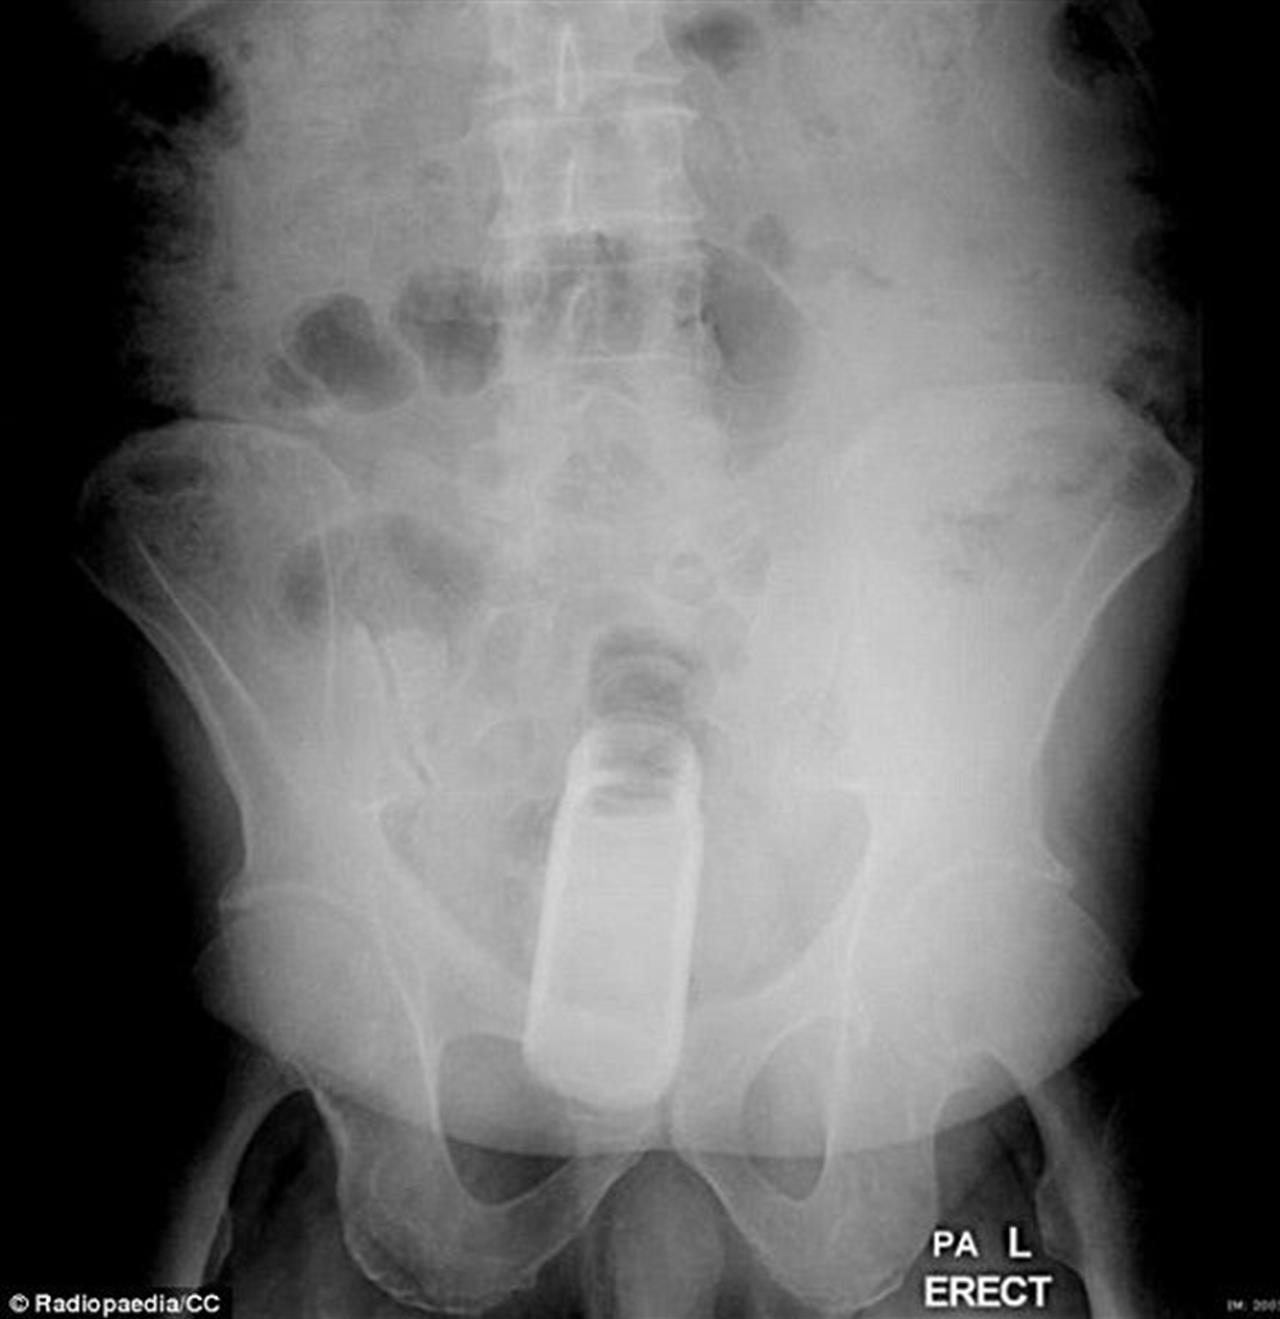

▼在這起案例中,這是一罐除臭劑!